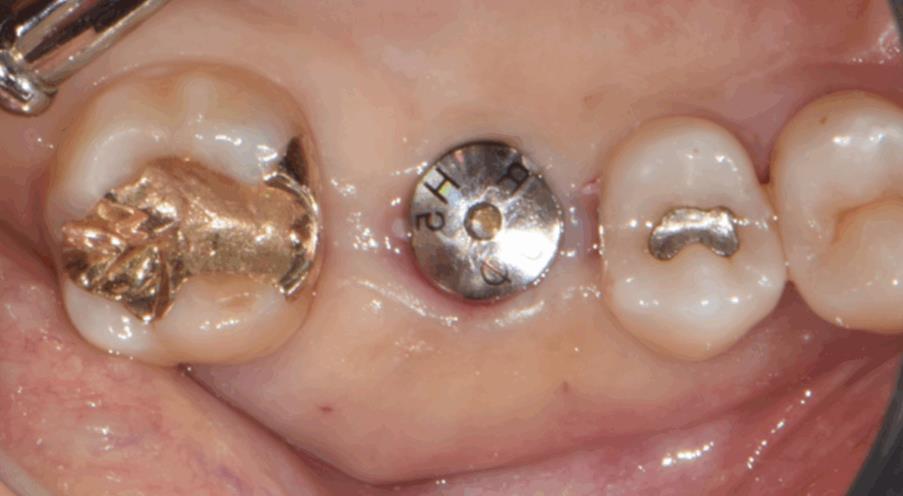

수술 직후 구내사진 – 절개 없이 깔끔하게 마무리된 수술 부위